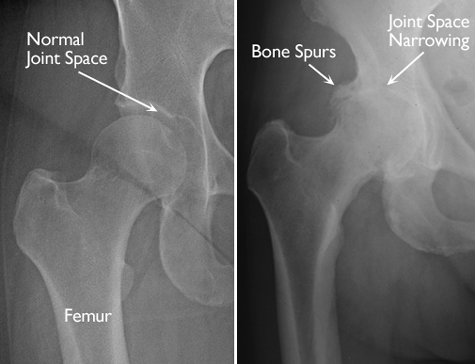

In osteoarthritis, the cartilage in the hip joint gradually wears away over time. As the cartilage wears away, it becomes frayed and rough, and the protective joint space between the bones decreases. This can result in bone rubbing on bone. To make up for the lost cartilage, the damaged bones may start to grow outward and form bone spurs (osteophytes).

X-rays. These imaging tests create detailed pictures of dense structures, like bones. X-rays of an arthritic hip may show a narrowing of the joint space, changes in the bone, and the formation of bone spurs (osteophytes).

(Left) In this x-ray of a normal hip, the space between the ball and socket indicates healthy cartilage. (Right) This x-ray of an arthritic hip shows severe loss of joint space and bone spurs.